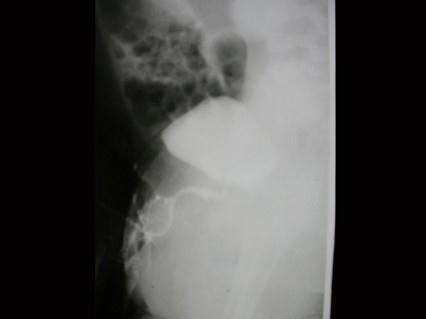

问题 男,4个月,阴茎、排尿异常4个月,行尿道造影如图所示,最可能的诊断是?(?)

选项 A.正常尿道 B.尿道瓣膜形成 C.尿道下裂畸形 D.尿道憩室 E.尿道重复畸形

答案 E